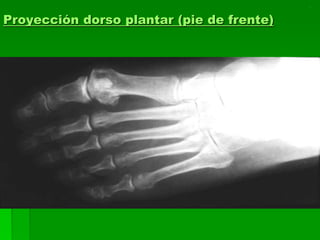

Proyección dorso plantar (pie de frente)

Proyección dorso plantar

 4: NAVICULAR

 5: CUNEIFORME

 6: BASE DEL PRIMER

MEATARSIANO

 7: CUERPO DEL 1º

METATARSIANO

 8: CABEZA DEL 1º

 9: HUESO SESAMOIDEO

 10: FALANGE PROXIMAL

 11: FALANGE MEDIA

 12: FALANGE DISTAL

1. Falange proximal 1 dedo

2. Base primer metatarsiano

3. Diáfisis primer metatarsiano

4. Cabeza primer metatarsiano

5. Huesos sesamoideos

6. Cuneiforme medial

7. Cuneiforme intermedio

8. Cuneiforme lateral

9. Escafoides

10. Tuberosidad del escafoides

11. Cabeza del talo

12. Maléolo lateral

13. Cuboides

14. Calcáneo

Pie de frente AP

 Posición del paciente: sentado

sobre la mesa radiográfica, la

pierna flexionada, apoyando la

planta del pie sobre el chasis.

 Rayo director: incide:

1-perpendicular al plano de apoyo

sobre la base del tercer

metatarsiano.

2-con angulación de 5º a 10º hacia

el tobillo, para visualizar antepié.

 Recomendaciones:

 DFP: 1mts.

 Película: 24x30 longitudinal.

 Diafragmar.

 Marcar el lado derecho.